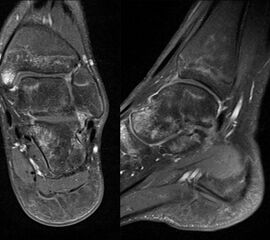

MRT

Die Kernspintomographie hat ihre Stärke in der Darstellung von Weichteilverletzungen. Insbesondere Verletzungen der Wachstumsfuge, des Periosts und der Bänder lassen sich gut visualisieren. Nachteilig ist die Untersuchungsdauer von 20-30 Minuten. Bleibt das Kind während dieser Zeit nicht ruhig liegen, kommt es zu Bewegungsartefakten, welche die Beurteilbarkeit der Bilder beeinträchtigen.

Osteochondrale Verletzungen

Osteochondrale Verletzungen können infolge eines Distorsionstraumas beobachtet werden (Taluskantenfraktur), teilweise lässt sich auch kein Trauma eruieren. Der es sich bei osteochondralen Verletzungen um keine Arthrose handelt, ist gerade bei Schmerzfreiheit ein defensives Vorgehen angezeigt. Bei offenen Wachstumsfugen kann eine osteochondrale Verletzung unter konservativer Therapie ausheilen.

Eine retrograde Anbohrung ist indiziert, wenn sich im MRT Verlauf eine zunehmende Sklerosierung im Randbereich der Läsion zeigt bei intakter Knorpeloberfläche.

Instabile Knorpelareale werden arthroskopisch entfernt in Verbindung mit einer Mikrofrakturierung der subchondralen Knochenlamelle.